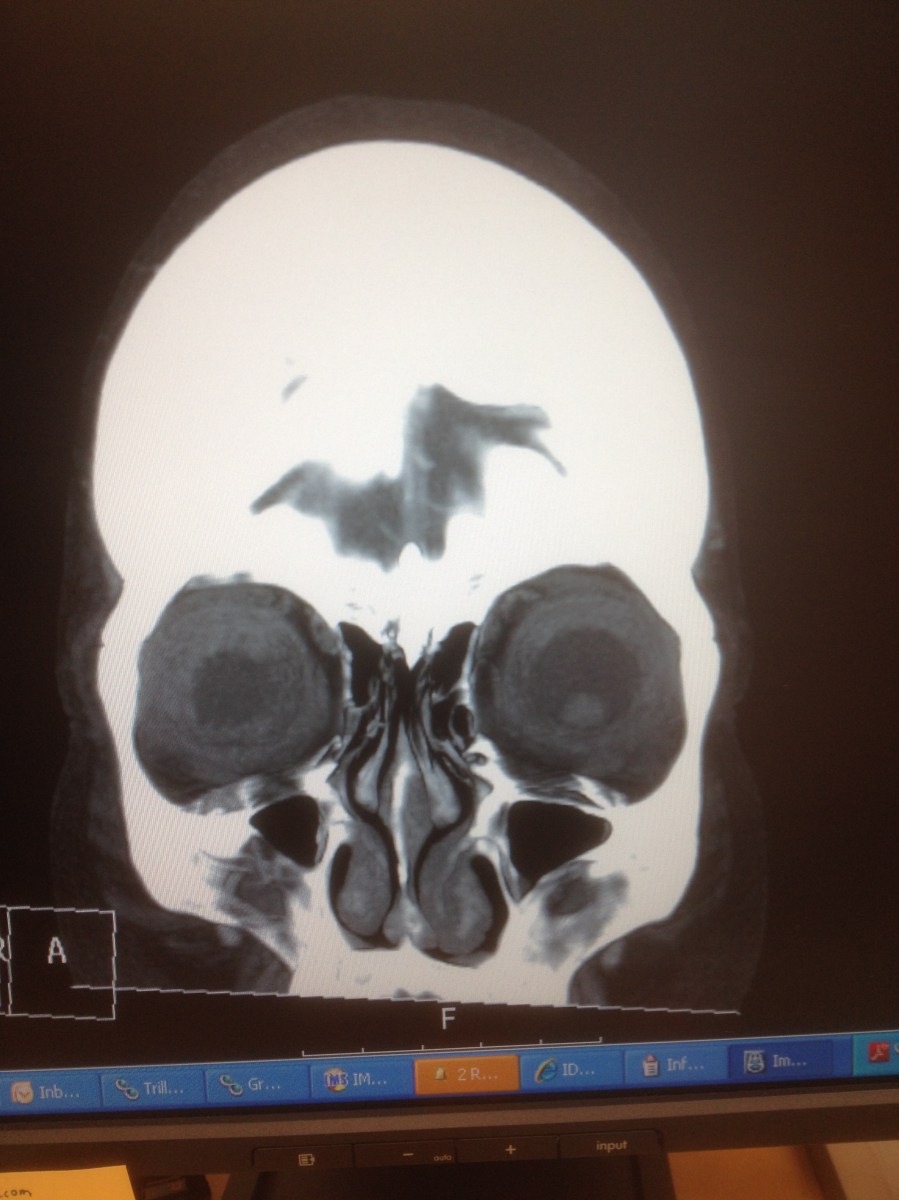

2014-03-13 13.31.41 Published October 21, 2018 at 2448 × 3264 in The oxen are slow, but the earth is patient ← Previous Next →